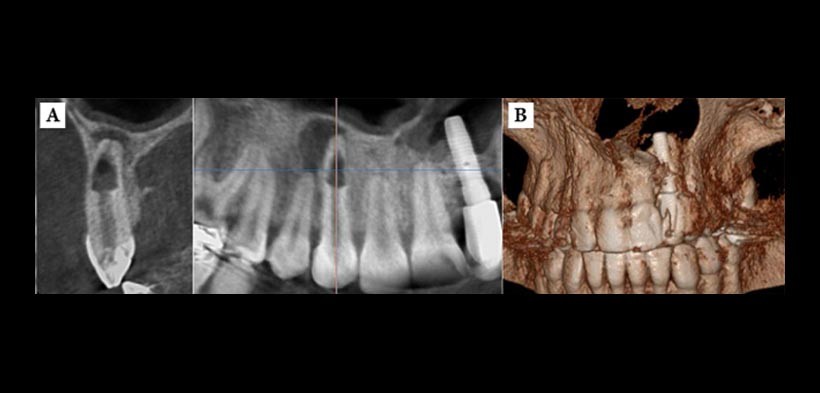

- REABSORCIÓN RADICULAR EXTERNA E INTERNA: Las lesión de resorción es desapercibido, hasta que se hace evidente en imágenes convencionales, y el daño consiguiente puede ya ser de mayores proporciones. En la actualidad CBCT es un menudo aplicado para evaluar el alcance de las reabsorciones radiculares sobre todo de la interna y nos ayuda para dar un mejor pronóstico del diente afectado (fig. 3).

(Figura 3. A) Se observa reabsorción radicular interna en el canino superior derecho: tenga en cuenta además la extensa reabsorción ósea adyacente al periápice lo cual indica la necrosis de la pieza dentaria; B) Reconstrucción tridimensional de la región.